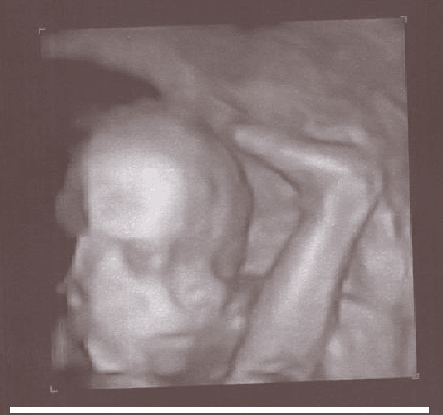

paulina cudny portrecik :-D

dzag, śliczności! Moja też ma inklinacje do zasłaniania się rączkami :tak: Mam ujęcia jedynie górnej części twarzy. Za nic nie chciała odciągnąć łapek (i to obu) od usteczek;-)

Anielka chciała się przywitać - zdjęcie z dzisiaj, czyli koniec 26 tygodnia :) Nochal trochę rozciągnięty, bo się ruszyła ;)